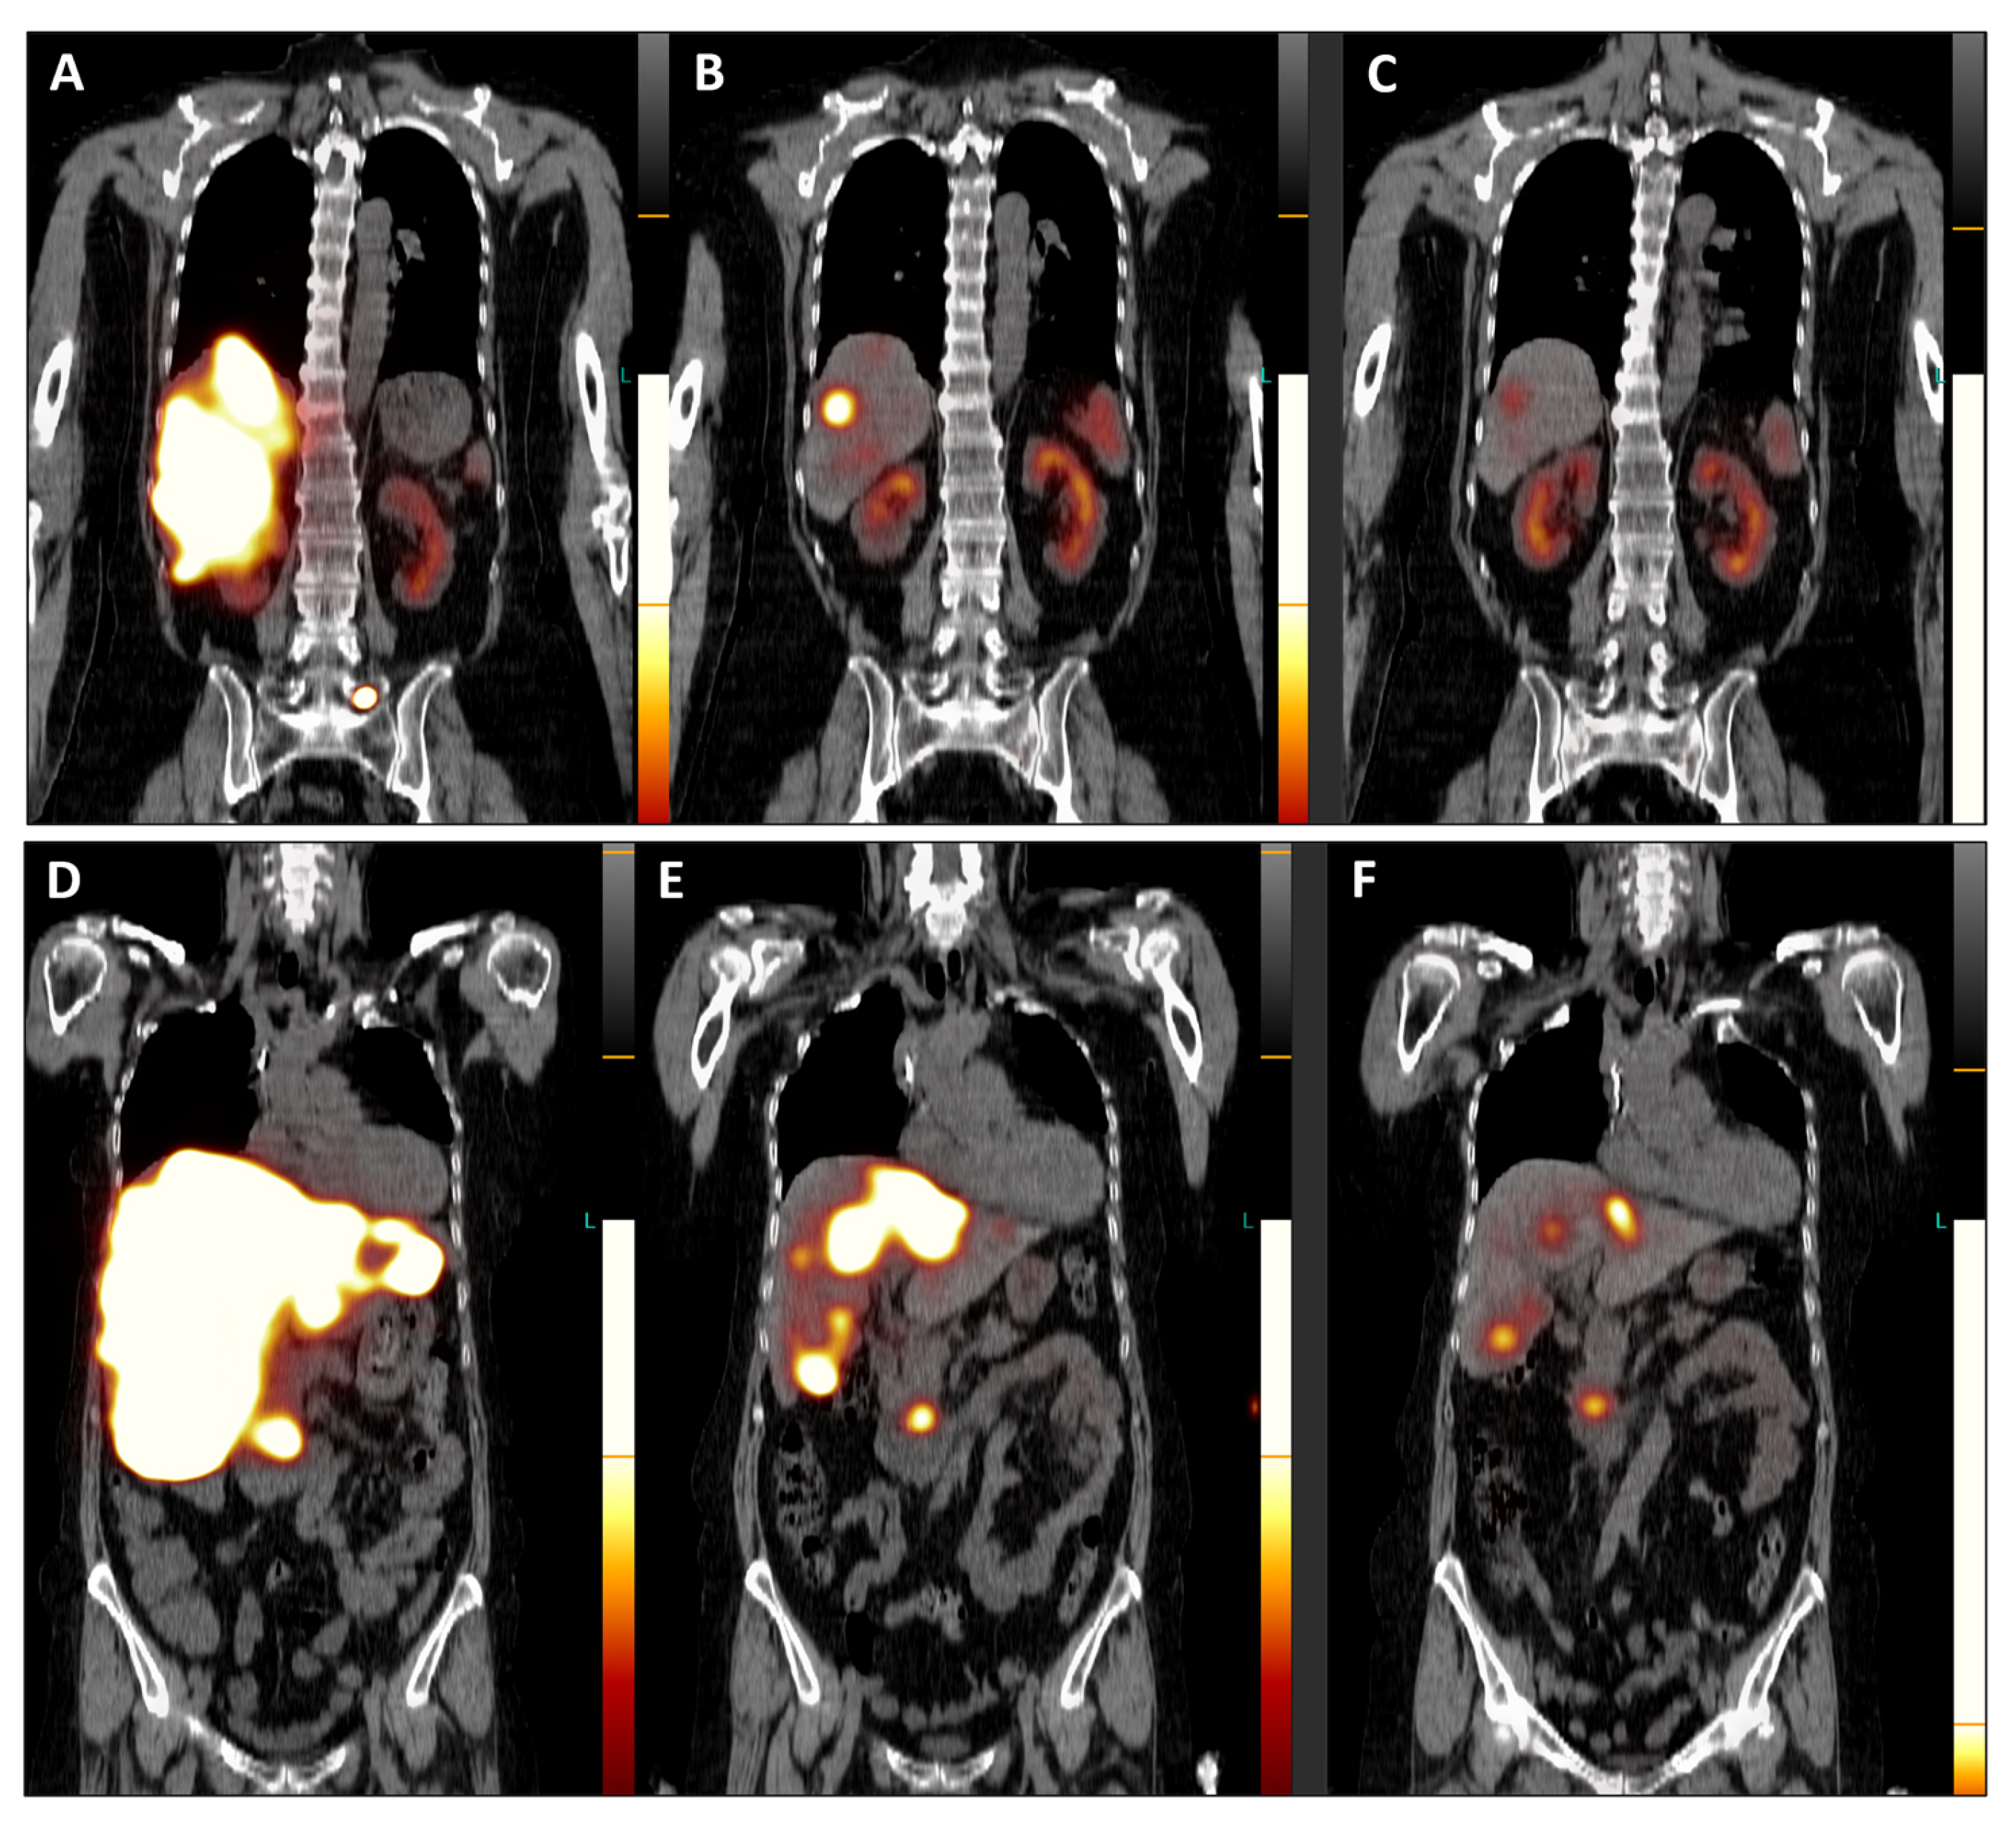

Figure 4. Post-therapeutic coronal SPET/CT scans ((A,D), July 2023; (B,E), September 2023; (C,F), November 2023) illustrate the remarkable improvement in hepatomegaly (with normalization of liver dimensions) and the exceptional reduction in SSTR antagonist uptake in the numerous disseminated metastases across both liver lobes (Figure 4). Additionally, the previously active metastatic lesion in the left transverse process of L5 is no longer visible (AC), and qualitative evaluation indicated a significant decrease in radiotracer uptake in the primary tumor of the pancreatic head (DF). Furthermore, semi-quantitative assessment using mean counts of the primary tumor mass and background (gluteus muscle) revealed a reduction in the tumor-to-background ratio throughout the TANDEM-PRRT courses, from 73.7 in July 2023 to 19.4 in November 2023.